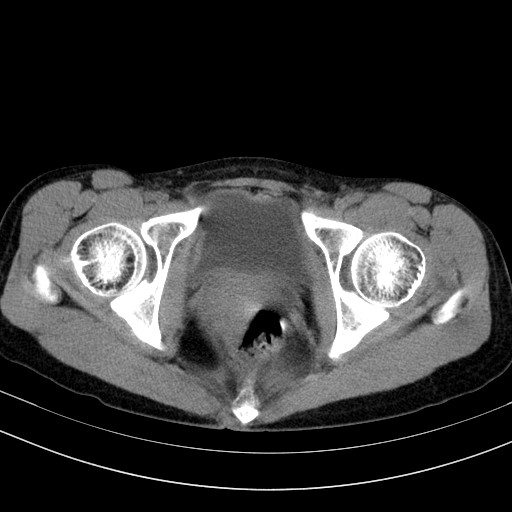

以下是引用卜一在2009-4-7 5:08:00的发言:[br]宫颈癌可能。支持!

以下是引用随光逐影在2009-4-7 8:17:00的发言:[br]考虑宫颈占位性病变(宫颈癌?);建议行进一步检查。

以下是引用jiangjing在2009-4-7 16:46:00的发言:[br]宫颈增大,结构不清,右侧附件区可疑囊样占位,建议增强及mri 检查